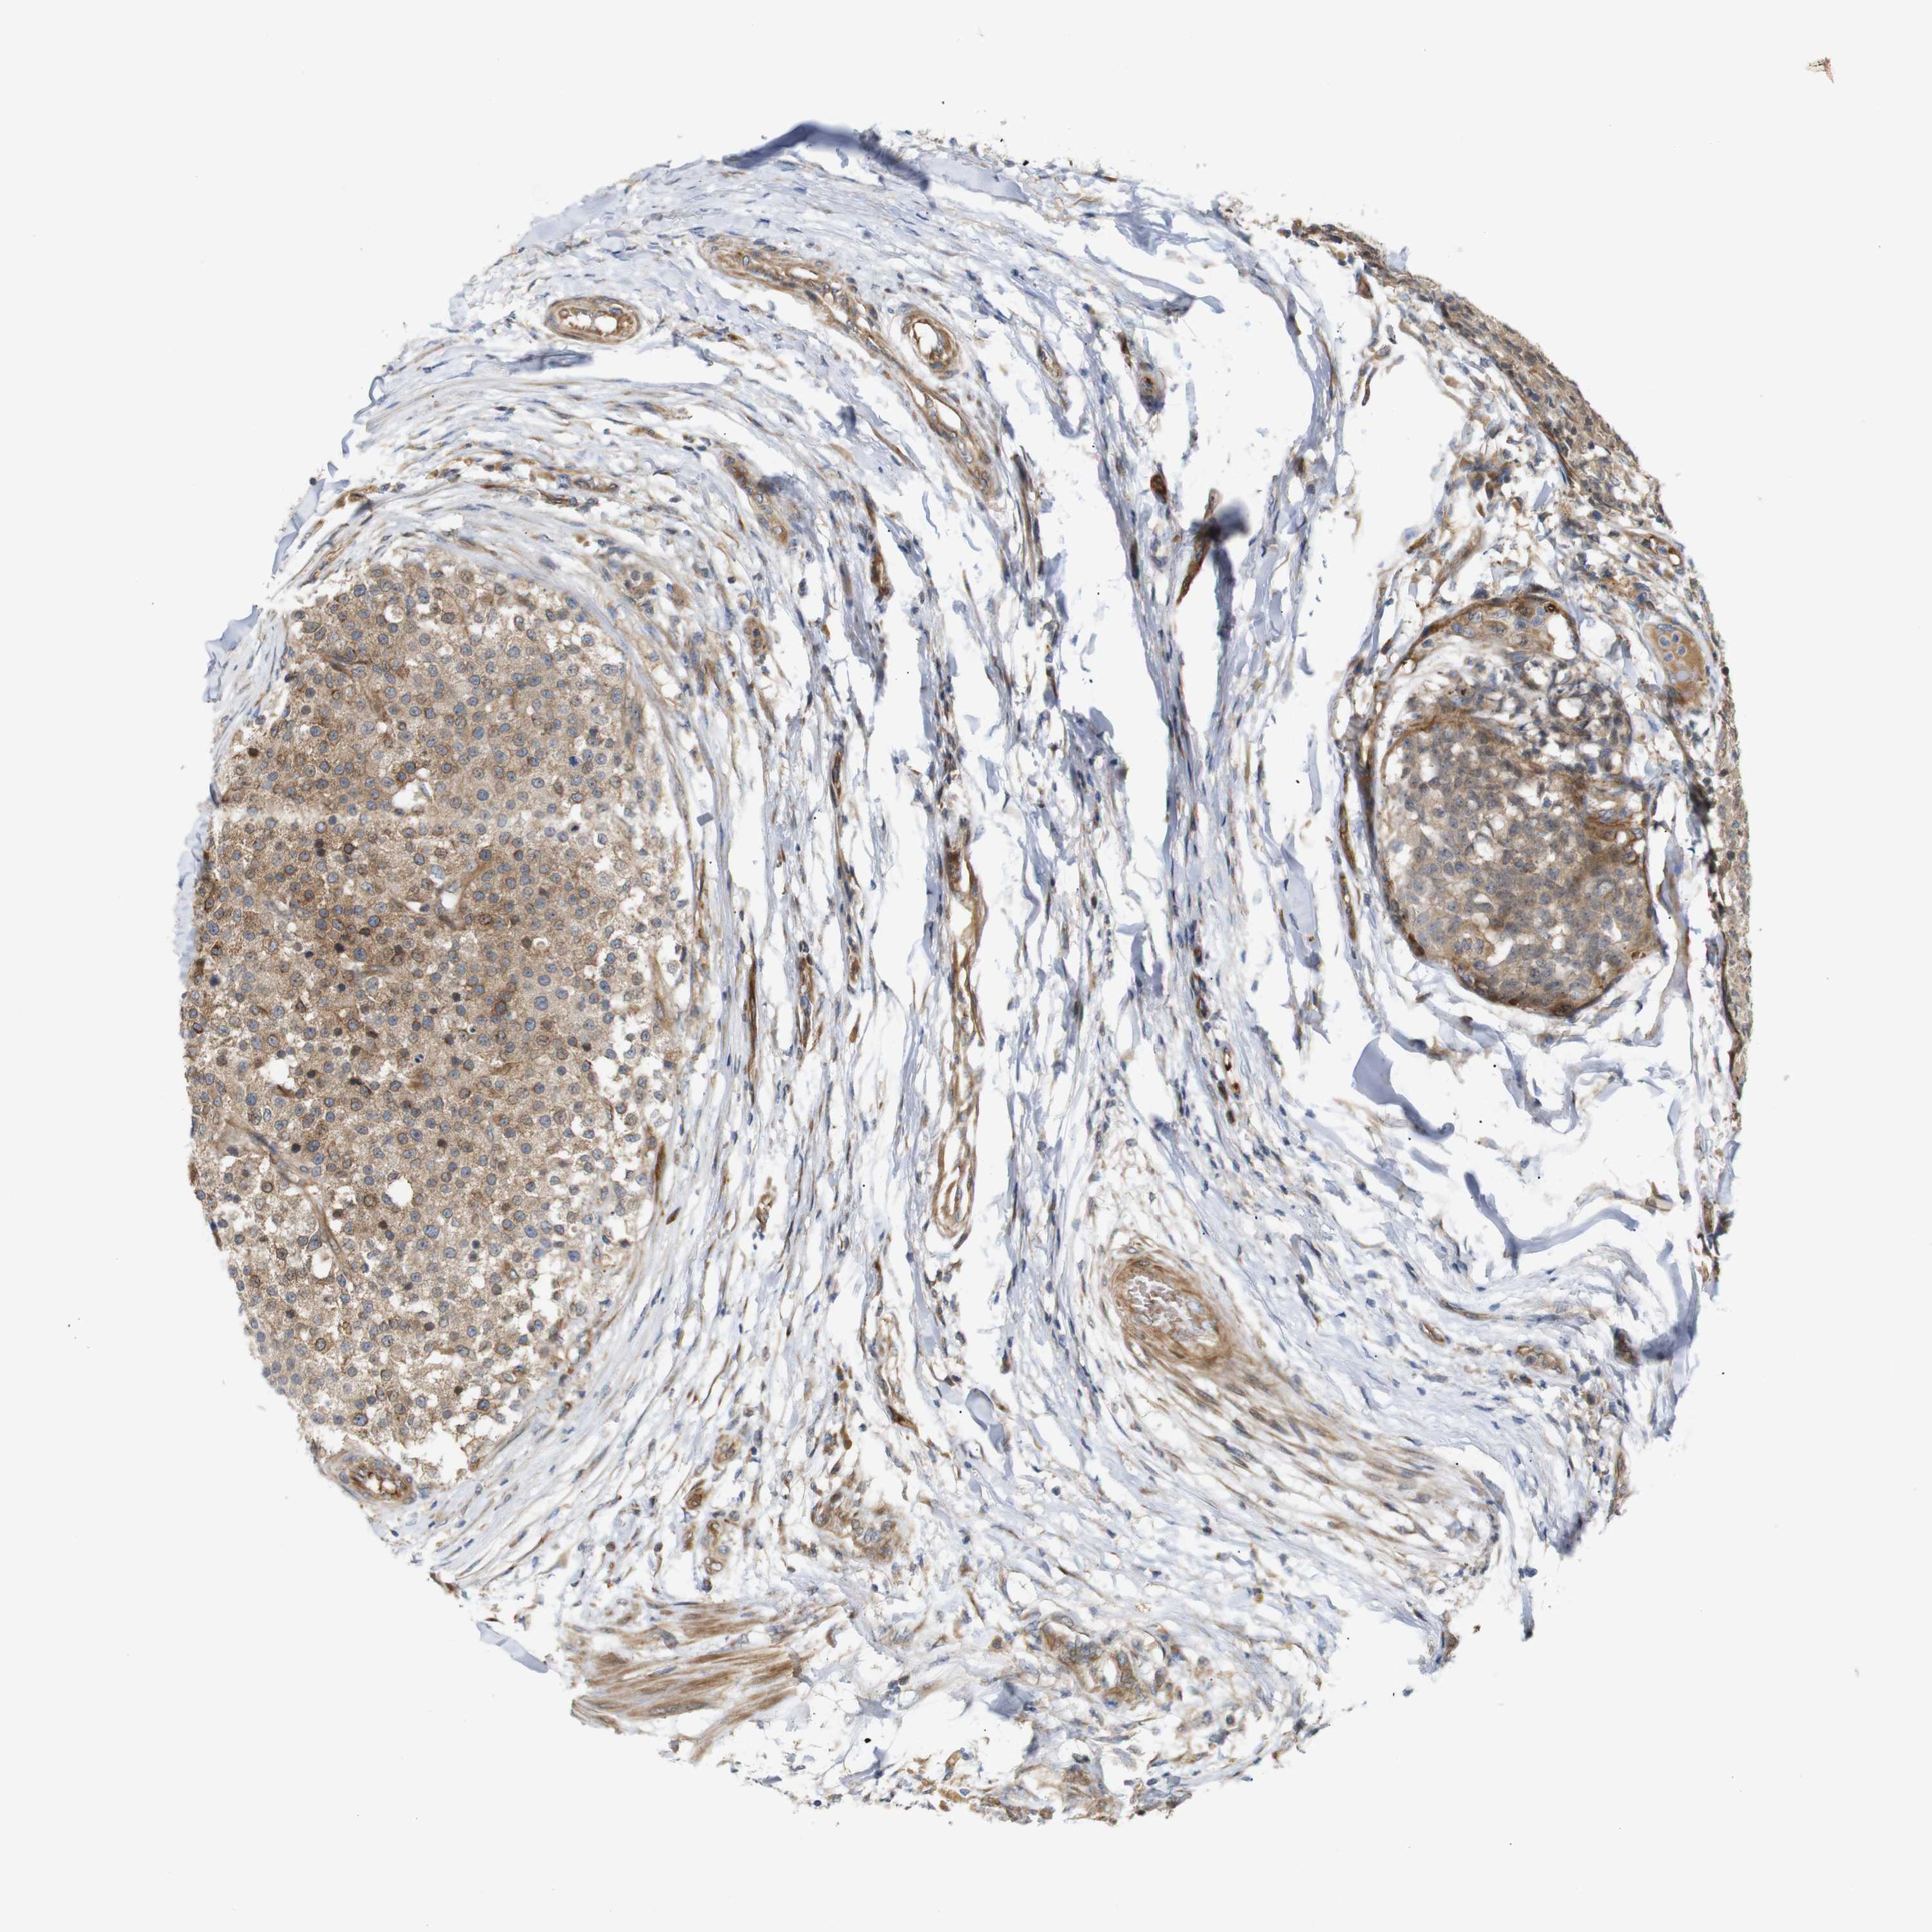

TESTIS CANCER - Protein expressioni

A mouse-over function shows sample information and annotation data. Click on an image to view it in a full screen mode. Samples can be filtered based on level of antibody staining by selecting one or several of the following categories: high, medium, low and not detected. The assay and annotation is described here.

Note that samples used for immunohistochemistry by the Human Protein Atlas do not correspond to samples in the TCGA dataset.

Antibody stainingi

Antibody staining in the annotated cell types in the current human tissue is reported as not detected, low, medium, or high, based on conventional immunohistochemistry profiling in selected tissues. This score is based on the combination of the staining intensity and fraction of stained cells.

Each image is clickable and will lead to virtual microscopy that enables deeper exploration of all samples and also displays staining intensity scores, fraction scores and subcellular localization as well as patient and tissue information for each sample.

Antibody CAB013514

Staining

High

Medium

Low

Not detected

Intensity

Strong

Moderate

Weak

Negative

Quantity

>75%

75%-25%

<25%

None

Location

Nuclear

Cytoplasmic/membranous

Cytoplasmic/membranous,nuclear

Carcinoma, Embryonal, NOS

Seminoma, NOS